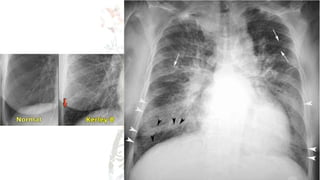

CHEST X RAY (CXR) Check for..

A – airways

B – basal lungs & pleura

C – cardio mediastinum

D – disabilities (visible fractures etc)

E – everything else

• R > L diaphragm gap (not more than 3cm)

• Cardiothoracic ratio not more than <55%

• Trachea diameter < 25mm in males/ < 21mm in females.

• Aortic notch should be visible.

• Any gastric abnormalities (bubbles)

CHEST X RAY(CXR) Check for.. A – airways B – basal lungs & pleura C – cardio mediastinum D – disabilities (visible fractures etc) E – everything else • R > L diaphragm gap (not more than 3cm) • Cardiothoracic ratio not more than <55% • Trachea diameter < 25mm in males/ < 21mm in females. • Aortic notch should be visible. • Any gastric abnormalities (bubbles)